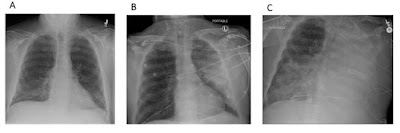

Progressão da radiografia de tórax em paciente com pneumonia

hemorrágica por S. maltophilia. A: Raio X de tórax portátil na admissão. B:

Raio-X torácico portátil pós-intubação, 36 horas após admissão no hospital. C: Raio-X

portátil de tórax 72 horas após a internação hospitalar.